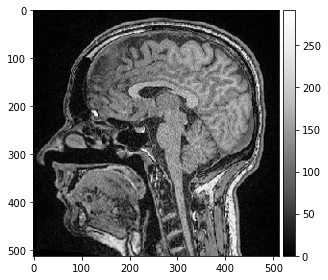

image = imread('../../data/Haase_MRT_tfl3d1.tif')

imshow(image[100])

image.shape

(192, 256, 256)